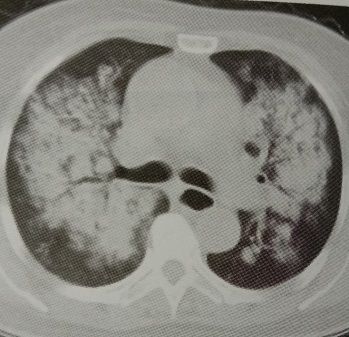

3.患者平素体健,近几日发热,咳嗽,CT如下:

这个蝶翼征太典型了,心衰合并肺部感染?

NO!像心衰,不一定是心衰。

抗细菌感染,病情好转。

这就是一个单纯的肺部感染!蝴蝶想他了。